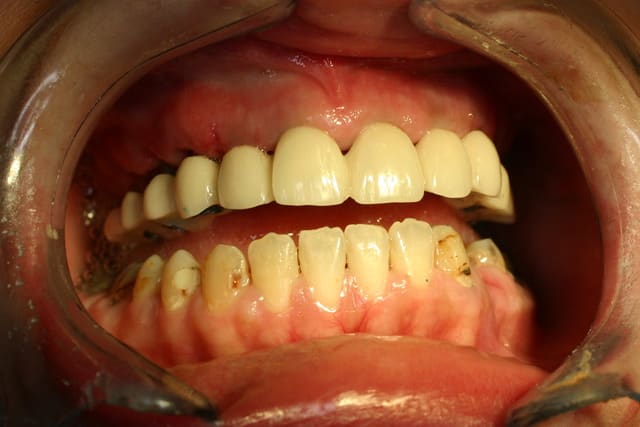

Néanmoins patiente traitée ...

Pp ;-)

Img 2224 reca asmlcg - Eugenol

Copie de img 2223 fdyqus - Eugenol

c'est le provisoire PP ?

Pépélaratiche

14/11/2010 à 12h55

Oui bien sûr placé sous 48 h

Les piliers seront retirés sur les molaires par la suite

Pp